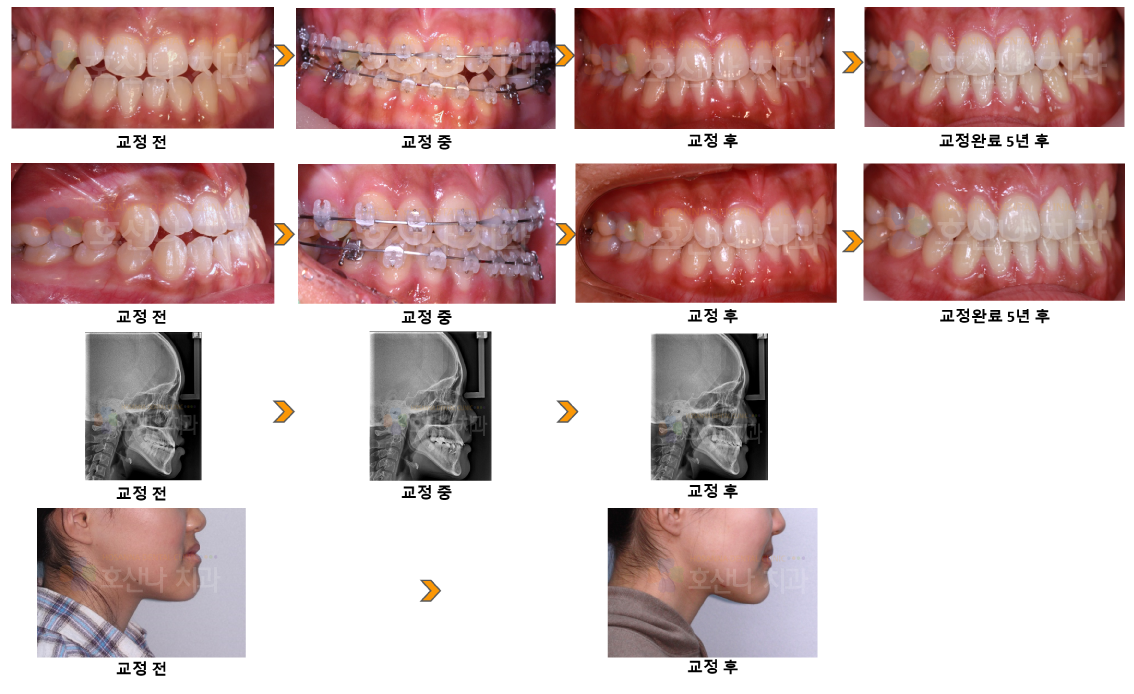

교정비대칭을 동반한 주걱턱교정 시술 증례

< 비대칭을 동반한 주걱턱교정 >

1. 치료대상

17y 4m

2. 교정치료이유

반대교합, 비대칭개선

3. 진단결과

1) Skeletal CL III open

2) Midline off

3) ant. Cross bite

4) Protrusion

5) III canine, molarrelation

4. Dr.Koo Memo

골격성 3급 부정교합과 비대칭 그리고 개방교합을 가진 환자분입니다.

돌출이 없고 수술을 원치 않기 때문에 발치 주걱턱교정으로 치료 계획을 잡았습니다.

얼굴이 길어지지 않게 하기 위해 수직적 조절을 고려하며

바른 치열과 교합 심미적 안모를 얻었습니다.

5년 후 f/u에 재발 없이 잘 유지된 모습입니다.

5.교정기간

1y 10m